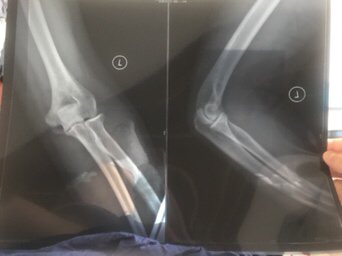

本身今年六月经历了一起车祸 造成股骨颈等 三处骨折 对方全责 ,买了一百万全险。保险公司给我列出个单子总共赔偿才18w左右,我光住院就大概花了八万,伤残鉴定月底去做。这个赔偿肯定不合理,都是按最低的算的。而且股骨颈是有坏死的可能性的。起诉的时候能不能把这条因素算进去 ,或者是以后出现后遗症可以追诉之类的,我不能让自己承担这个风险啊。请有经验的给我说说这个流程 ,还有哪些可以在起诉中提到的有利条件。 谢谢大家。